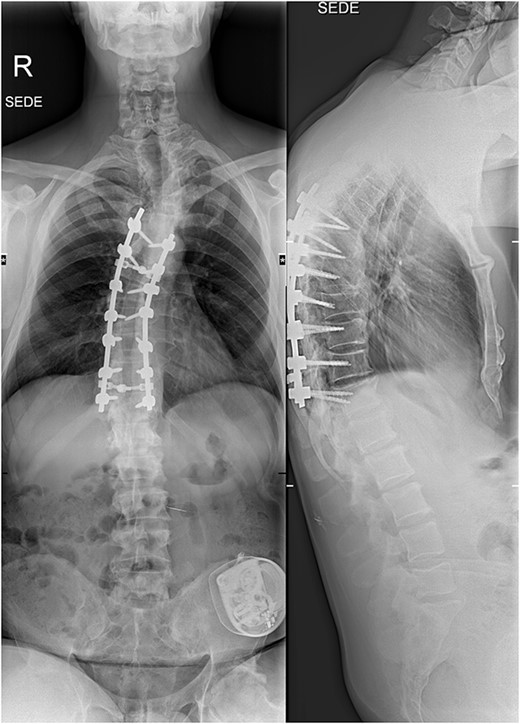

Six weeks after surgery he was transferred to a tertiary rehabilitation center, ambulating using a walker, but remained wheelchair-bound for longer distances. The postoperative pain was manageable with non-opioids. During the regular follow-ups, the paraplegia with severe spasticity persisted, without significant pain. A subsequent insertion of the intrathecal baclofen pump in a tertiary rehabilitation facility enabled the patient to manage the muscle spasms in his lower limbs, particularly during transfers from the wheelchair to bed and vice versa. The patient was able to urinate spontaneously with minimal urine retention, and no need for self-catheterisation, reporting satisfaction with the outcome of the surgery and rehabilitation, which enabled him a return to his workplace and retain a significant level of independence in everyday activities. On the final follow-up imaging, 4 years after the surgery, no significant deformity progression and no evidence of neurologic impairment were observed (Figs 4 and 5).

X-rays at the final follow-up 4 years after the surgery. Anteroposterior view (left) and lateral view (right).